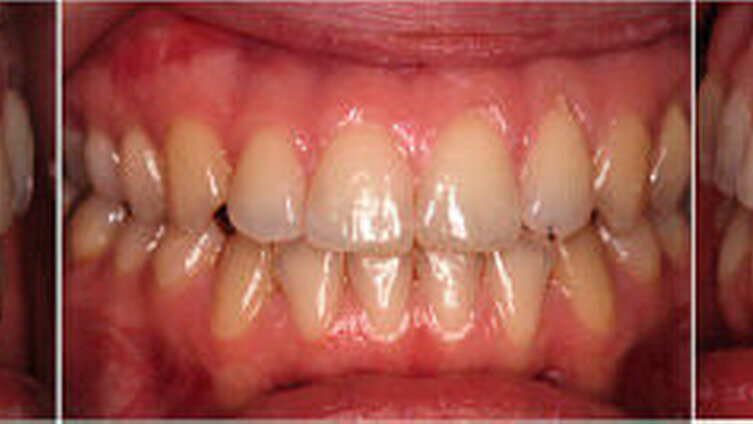

Die Patientin war zu Behandlungsbeginn 26 Jahre alt. Sie wies eine ausgeprägte skelettale Mesialbisslage (Wits: – 15,6 mm) mit retrognather Maxilla (SNA: 76°) und prognather Mandibula (SNB 87°) bei zusätzlicher Mittelgesichtshypoplasie auf (Abbildung 1a). Intraoral bestanden ein frontal offener Biss und eine transversale Enge im Oberkiefer mit zirkulärem Kreuzbiss (Abbildung 1b).